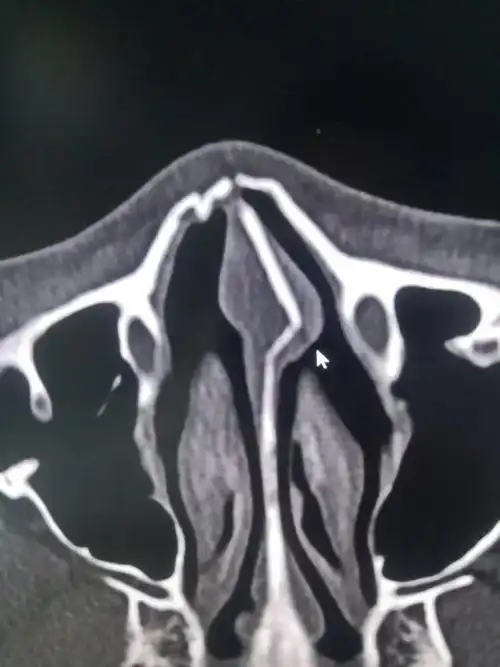

鼻骨解剖及ct诊断